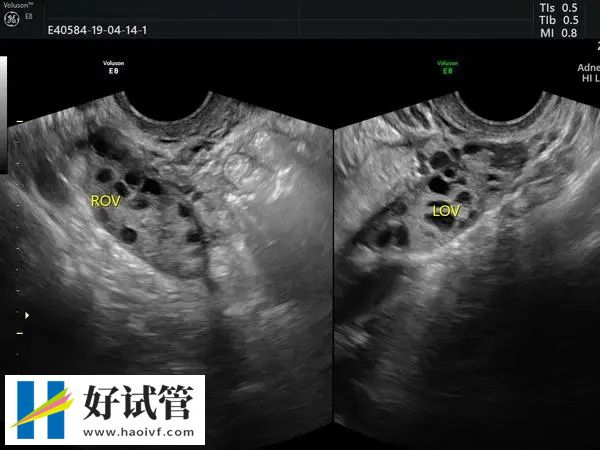

促排药能够刺激女性卵巢排放更多的卵泡,增加成功率。这些药物通常由注射或口服给予。在这个过程中需要密切监视女性身体情况,包括血液激素水平和超声检查。

在促排5天后需要再次返院检查看卵泡的大小,如果卵泡的大小已经达到18-20mm的话,那么就需要打夜针,一般就是使用艾泽或者是达必佳促进卵泡的最终成熟。